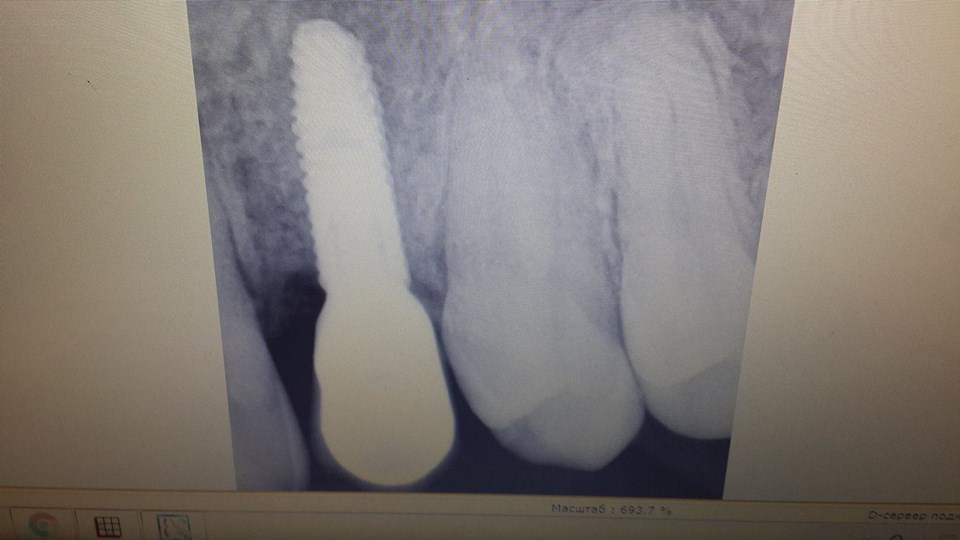

Canine restoration using implantation

To successfully restore the canine, the patient was simultaneously removed a tooth and used bone material.